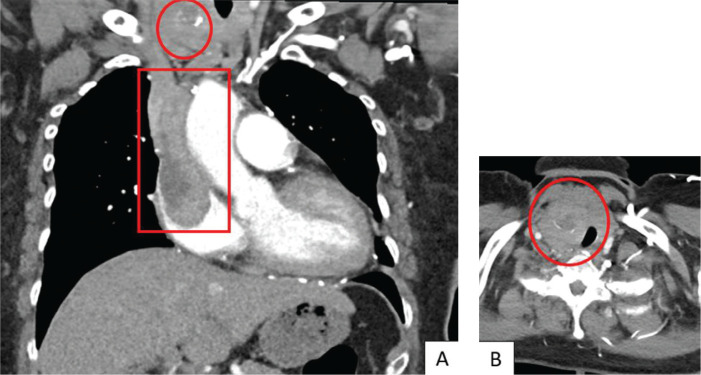

We report a case of an uncommonly aggressive presentation of the rare entity of synchronous papillary (PTC) and follicular thyroid carcinomas (FTC) in a 67-year-old female initially presenting with thyrotoxicosis from Graves' disease. She was found to have two thyroid nodules with extensive intra-cardiac tumour thrombus, symptomatic left pelvis bony metastasis with pathological fracture, pulmonary metastases and mediastinal lymph node metastases. Further investigations suggested a diagnosis of synchronous papillary and metastatic follicular thyroid cancer. Treatment with radical surgery followed by adjuvant therapeutic radioiodine ablation was proposed, but the patient declined all forms of cancer-specific therapy and was elected solely for a palliative approach to treatment. We discuss the diagnostic considerations in arriving at the diagnosis of synchronous thyroid malignancy - in this case the clear features of PTC and the strong probability of FTC due to invasiveness and metastatic follicular lesions. This case underscores potential limitations of the ACR TI-RADS system, notably with certain ultrasonographic features suggesting malignancy that might not be adequately captured. Notably, the aggressive presentation of DTC in this case may be contributed by the concurrent presence of Graves' Disease, suggesting heightened vigilance when assessing potential thyroid malignancies in such patients.